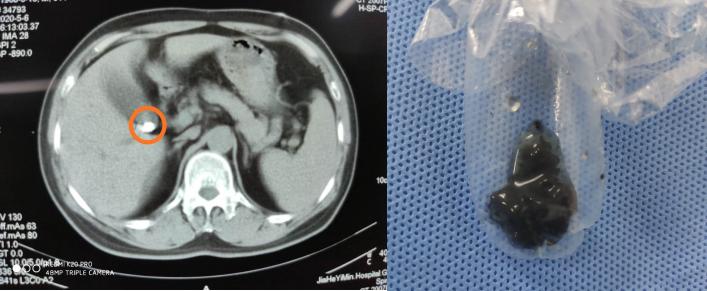

徐女士术前CT片 术后取出的结石标本

在广药三院外六科,经过胆囊的影像检查,接诊专科梁法生博士进行了术前评估,认为患者胆囊功能良好,具有保胆手术的指征,于是制定了保胆手术治疗方案。即采用双镜联合保胆取石术。8月26日,广药三院外六科梁法生博士及团队为徐女士施行了该手术,采用腹腔镜和胆道镜双镜联合,腹部仅2个5mm以内的小切口,在腔镜可视条件下将胆囊结石悉数取出,手术过程顺利,手术非常成功,胆囊完整保留。术后四天复查肝胆彩超,均未见异常,遂已出院。主诊及主刀专家梁法生博士介绍说,双镜联合微创保胆取石术,创伤很小,腹部2~3个5毫米创口,胆囊上仅一个4mm小切口就能清除所有结石,缝合一针即可,不影响腹腔脏器。且住院时间短、恢复快,4天康复即可出院。